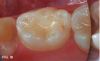

Case 3. This 10-year-old boy was brought to the office for a second opinion regarding restoration of the left primary first molar, which was causing sensitivity (Figure 8). The boy's mother reported that a "tooth-colored filling" had been suggested at another office. The boy was terrified of needle injections and, according to his mother, had required sedation in prior years for restoration of maxillary primary molars. SDF was applied (Figure 9), tooth sensitivity was eliminated, and in 3 months, clinical evaluation and a periapical radiograph confirmed that no other treatment would be needed until the tooth exfoliated (Figure 10 and Figure 11).

Fig 10. 3 months after SDF application, no additional treatment needed.

Fig 10

Fig 11. 3 months after SDF application, no additional treatment needed.

Fig 11